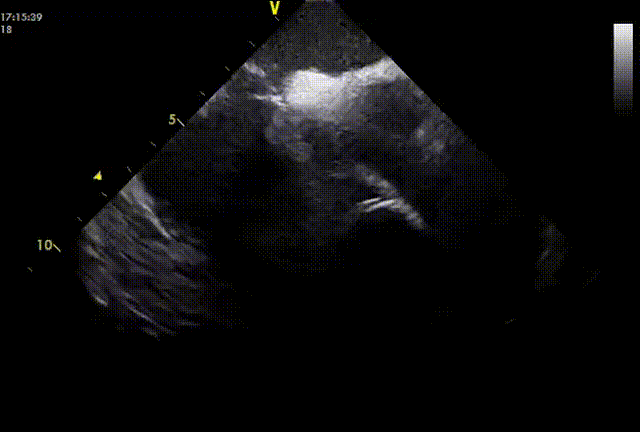

封堵盘展开